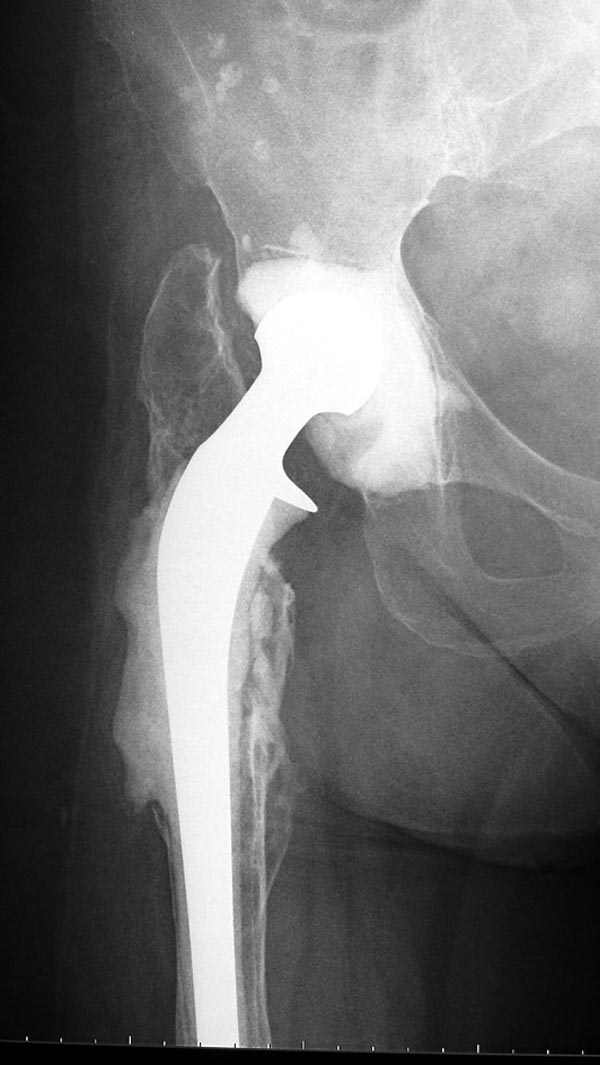

Этот вариант функционально более перспективен, асбсолютно оправдано двухэтапное эндопротезирование с установкой на первом этапе

артикулирующего спейсера: чашка изготавливается из цемента (гентамицин+ванкомицин) ножку лучше взять типа Элит Плюс, на тот же вариант цемента с а/б. Подводных камней так же хватает: необходима

тщательная ХО, максимальное сохранение мышц (тут масса нюансов и ориентироваться придется по ходу операции), длительная направленная а/б терапия..... Но на мой взгляд, на перспективу реабилитации это лучший вариант. Если нужна большая детализация техники установки спейсера -

напишу. Реальная результативность таких операций 90-95%

Из предложенных вариантов быстрейший результат можно ожидать после поэтапного эндопротезирования.

"Антибиотико-цементные" спейсеры после купирования

инфекции уже после первого этапа позволяют больным

передвигаться самостоятельно, иногда нагружая конечность годами.

Как-то показывал случай после осложненного тотального эндопротеза, сперва из-за отсутствия экономических возможности, а затем привыкшая к своей участи вот уже более 8 лет ходит на временном "протезе-спейсере".

Полость вертлужной впадины и проксимальное бедро были заполнены custom made временным протезом из цемента.

Для бедренного компонента можно применить старую

длинную ножку протеза и желательно малого диаметра.

Цементная смесь наносится вручную на металл и

затем доводится до ровного диаметра поверхности

снятием лишнего цемента шаблоном. Такие шаблоны были в старом интрамедуллярном наборе, различные по диаметру отверстия на металлической пластине. Протез с цементом проводится через отверстие в шаблоне для точного совпадения с размером проксимального римера. Таким образом приготовленный феморальный компонент будет

держаться в бедренной кости плотно.

В зависимости от процесса дозу антибиотика можно

увеличить в два раза: Tobramycin 2.4 gm Vancomycin 2 mln. На такое количества порошка для получения

нормальной полимеризации цемента необходимо добавить дополнительную цементную жидкость.

В вертлужную полость устанавливается цемент и головкой протеза выдавливается выемка, т.е. создается место для головки. В проксимальное бедро устанавливается заранее подготовленный цементный бедренный компонент.

Через пару месяцев после улучшения мягкотканой

кондиции можно приступить к окончательному протезу.